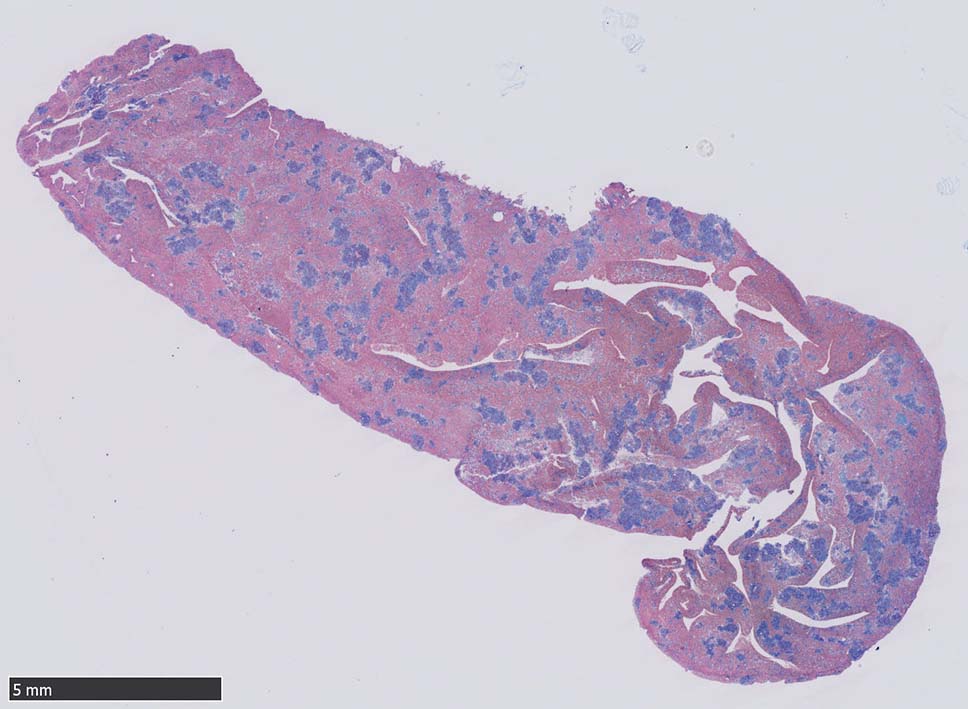

肝臓  サムネイルのクリックで大きな画像が見られます.

肝針生検組織; 類洞に細胞浸潤が認められ, 非浸潤部との境界がぼんやりと認められる. 類洞と異なり, グリソン鞘は腫瘍細胞の浸潤が乏しいか, ほとんど認められない.

骨髄浸潤所見

同じ患者さんの骨髄所見です. (サムネイルのクリックで大きな画像が見られます.)

骨髄への腫瘍細胞浸潤はintertrabecular patternで, 腫瘍細胞は小集簇巣を形成して散在性に認められた. HE, ASD-Giemsaのみでの浸潤, 増殖の確定はなかなか難しいようです.